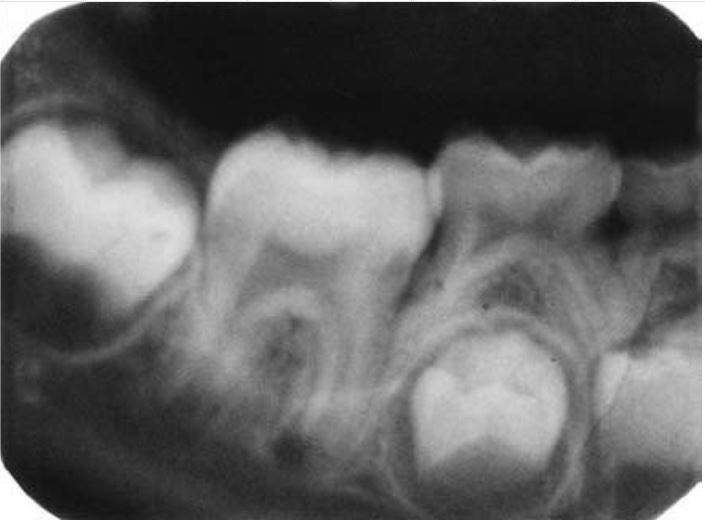

Răng bò mộng

Răng có dạng hình bò, thân răng lớn và chân răng ngắn, xảy ra trên các răng nhiều chân.

Răng có buồng tủy giãn dài, hình chữ nhật trong khi chân răng lại rất ngắn, không có điểm thắt tại đường nối men – cement. Răng vĩnh viễn bị ảnh hưởng nhiều hơn răng sữa, răng cối lớn nhiều hơn răng cối nhỏ.

Răng bò mộng thường gặp ở những bệnh nhân mắc các hội chứng di truyền như Down, Mohr, Klinefelter, ở trẻ đang điều trị ung thư.